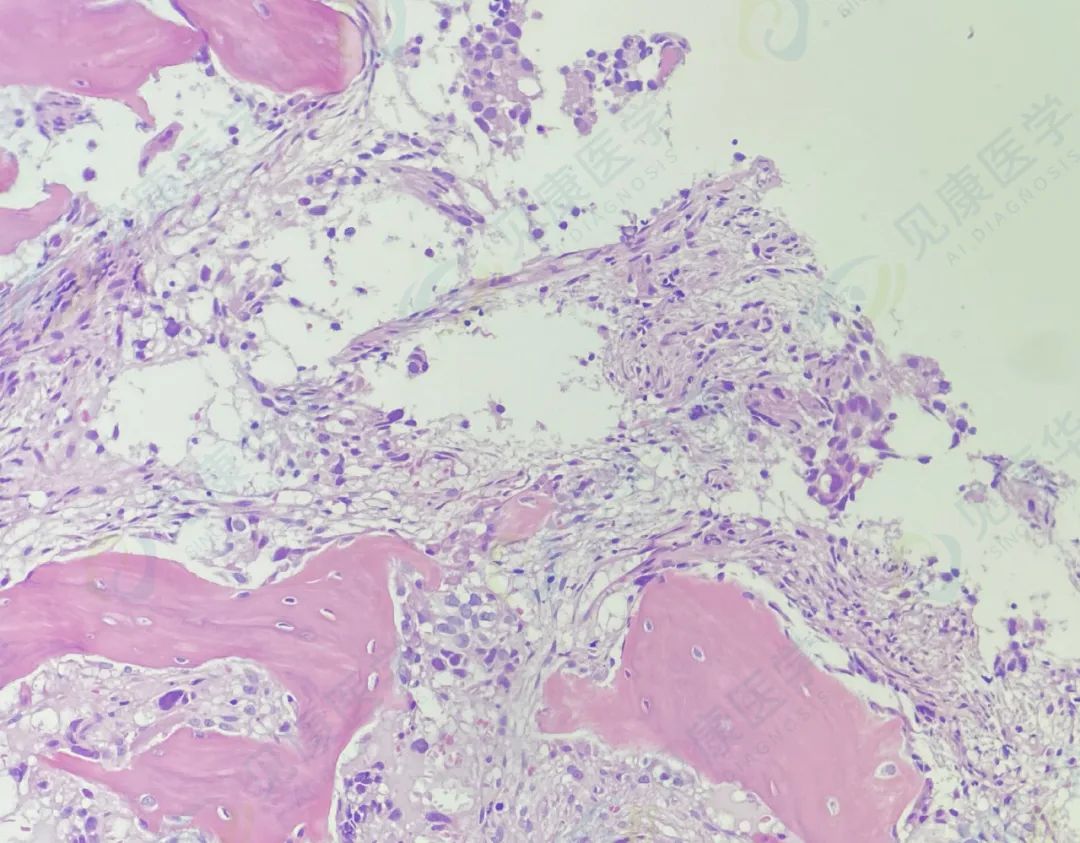

【形态学病例分享】第八十期

男,82岁, 既往诊断前列腺癌, 血尿1周。

病理HE染色

病理

AML-M2伴骨髓转移癌